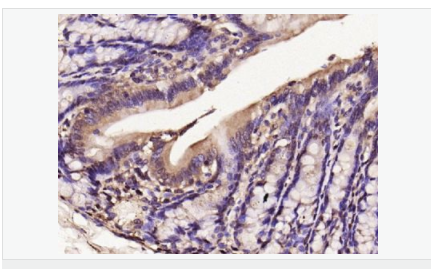

交叉反應(yīng):Human,Mouse,Rat(predicted:Dog,Pig,Horse,Sheep) 推薦應(yīng)用:WB,IHC-P,IHC-F,ICC,IF,Flow-Cyt

| 產(chǎn)品應(yīng)用 | WB=1:500-2000 IHC-P=1:100-500 IHC-F=1:100-500 Flow-Cyt=1μg/Test ICC=1:100-500 IF=1:100-500 (石蠟切片需做抗原修復(fù)) not yet tested in other applications. optimal dilutions/concentrations should be determined by the end user. |